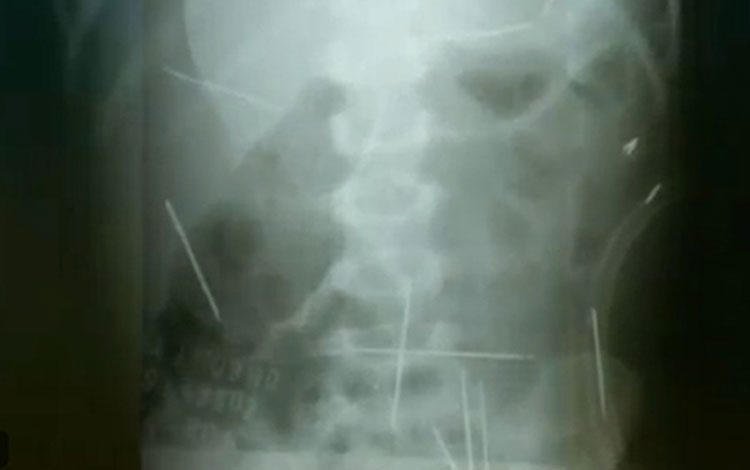

Após 9 anos, criança tem 4 agulhas das 31 enfiadas por padrasto em Ibotirama Foto: Reprodução/TV Globo

O menino que teve 31 agulhas inseridas no corpo pelo ex-padrastro, em 2009, ainda convive com quatro dos objetos dentro do corpo, nove anos após o caso. Hoje, com 11 anos, a criança ainda é acompanhada por médicos, depois de ter passado por três cirurgias, quando ainda tinha dois anos. O caso aconteceu em Ibotirama, no oeste da Bahia, e ganhou repercussão no mundo inteiro. O garoto deu entrada no hospital chorando e sentindo muitas dores, quando tinha 2 anos e 7 meses. Sem diagnóstico evidente, os médicos pediram uma radiografia e encontraram as 31 agulhas espalhadas pelo corpo do menino. Atualmente, a criança vive bem e com boa saúde. Ele estuda, brinca com os irmãos e participa de projetos sociais. As agulhas que ainda restam no corpo não oferecem risco à saúde, porque elas não mudam de lugar. Maria Souza Santos, mãe do garoto, que acompanhou todo o sofrimento do filho, está aliviada de ver o menino tão cheio de saúde. “Isso é um sonho, ver meu filho amparado, indo para a escola, brincando com o irmão, com os amiguinhos. Porque eu pensava naquilo que ele estava passando, que meu filho ia se acabar naquela hora por causa de mãos de gente ordinária, que não tem coração”, disse Maria, emocionada.